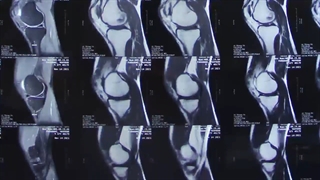

جراحی رباط صلیبی

از شایع ترین آسیب های زانو، کشیدگی و پارگی رباط صلیبی است که با کوچکترین نشانه و درد در ناحیه زانو باید حتما به متخصصص ارتوپد مراجعه کنید .